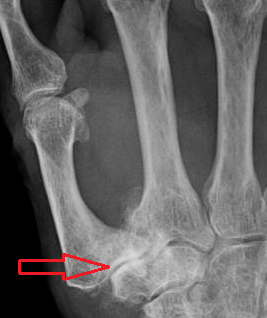

Classification according to Eaton and Littler[22]

CMC OA can be divided into different stages which show the progression of the disease. The most commonly used classification is the radiological staging protocol according to Eaton and Littler. Four different stages are distinguished on radiological evidence of synovitis, joint space and capsular laxity.[20]

Stage 1:

- "synovitis phase"

- slight widening of the joint space

- articular contours are normal

- < 1/3 subluxation of the joint (in any projection)

Stage 2:

- There is a significant capsular laxity

- 1/3 subluxation of the joint

- Osteophytes, < 2 mm in diameter, are present. (usually adjacent to the volar or dorsal facets of the trapezium)

Stage 3:

- > 1/3 subluxation of the joint

- Osteophytes, > 2 mm in diameter, are present (usually adjacent to the volar and dorsal facets of the trapezium)

- Slight joint space narrowing

Stage 4:

- Major subluxation of the joint.

- Very narrow joint space

- Cystic and sclerotic subchondral bone changes are present

- Significant erosion of the scaphotrapezial joint.